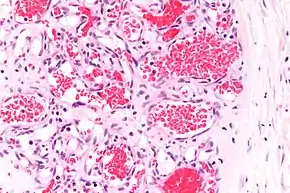

A precise history of the growth characteristics of the IH can be very helpful in making the diagnosis. In the first 4 to 8 weeks of life, IHs grow rapidly with primarily volumetric rather than radial growth. This is usually followed by a period of slower growth that can last 6–9 months, with 80% of the growth completed by 3 months. Finally, IHs involute over a period of years.[34] The exceptions to these growth characteristics include minimally proliferative His, which do not substantially proliferate[33] and large, deep IHs in which noticeable growth starts later and lasts longer.[34] If the diagnosis is not clear based on physical examination and growth history (most often in deep hemangiomas with little cutaneous involvement), then either imaging or histopathology can help confirm the diagnosis.[31][35] On Doppler ultrasound, an IH in the proliferative phase appears as a high-flow, soft-tissue mass usually without direct arteriovenous shunting. On MRI, IHs show a well-circumscribed lesion with intermediate and increased signal intensity on T1- and T2-weighted sequences, respectively, and strong enhancement after gadolinium injections, with fast-flow vessels.[31] Tissue for diagnosis can be obtained via fine-needle aspiration, skin biopsy, or excisional biopsy.[36] Under the microscope, IHs are unencapsulated aggregates of closely packed, thin-walled capillaries, usually with endothelial lining. Blood-filled vessels are separated by scant connective tissue. Their lumina may be thrombosed and organized. Hemosiderin pigment deposition due to vessel rupture may be observed.[37] The GLUT-1 histochemical marker can be helpful in distinguishing IHs from other items on the differential diagnosis, such as vascular malformations.[32]